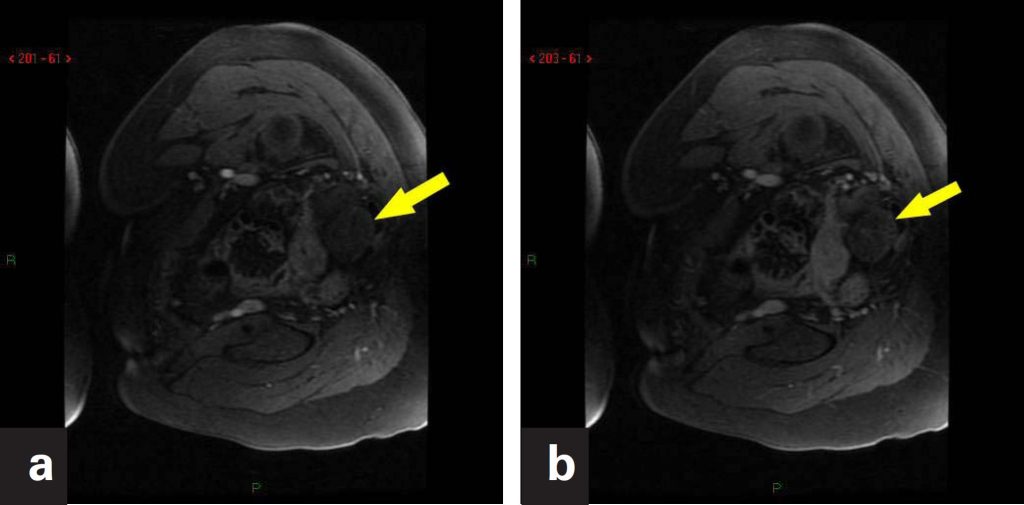

Adnexial torsion is an unusual event, but a major cause of abdominal pain in women. It is often associated with ovarian tumor or cyst, but can occur in normal ovaries, especially in children. The twisting of adnexial structures may involve the ovary or tube, but frequently affects both. In most cases, it is unilateral, with slight predilection for the right side. In imaging findings, increased ovarian volume and adnexial masses are observed, with reduced or absent vascularization. In cases of undiagnosed or untreated complete twist, hemorrhagic necrosis may occur leading to complications; in that, peritonitis is the most frequent. Early diagnosis helps preventing irreversible damage with conservative treatment, thereby saving the ovary. Limitations in performing physical examination, possible inconclusive results in ultrasound and exposure to radiation in computed tomography makes magnetic resonance imaging a valuable tool in emergency assessment of gynecological diseases. The objective of this study was to report two confirmed cases of adnexial twist, emphasizing the contribution of magnetic resonance imaging in the diagnosis of this condition.